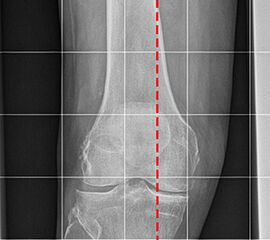

Aufnahmen zur Bestimmung der Bein- und Rückfussachse

Einbeinstandaufnahme

Positionierung:

• Der Patient steht auf beiden Füßen mit gleichmäßiger Lastverteilung.

• Die Kassette befindet sich dorsal des Beins und steht senkrecht zum Boden.

• Die Fußlängsachse verläuft nach ventral.

• Um Verzerrungen zu reduzieren wird die Aufnahme in 3 Teilaufnahmen angefertigt und die Bilder danach digital zusammengefügt.

• Die erste Aufnahme umfasst die Region vom Beckenkamm bis proximales Drittel des Femurs. Der Zentralstrahl ist auf das Hüftgelenk zentriert.

• Die zweite Aufnahme umfasst die distalen zwei Drittel des Femurs und das proximale Viertel der Tibia. Der Zentralstrahl ist auf das Kniegelenk zentriert.

• Die dritte Aufnahme umfasst die distalen Dreiviertel der Tibia mit Fuß und Sprunggelenk. Der Zentralstrahl ist wird mittig auf das Sprunggelenk zentriert.

• Die Röntgenröhre steht bei allen drei Aufnahmen 0° horizontal

Kennzeichen des Röntgenbildes:

• Abbildung des gesamten Beins.

• Die Aufnahme ist Basis aller Achskorrekturen.

• Zur Bestimmung der Beinachse wird die Mikulicz-Linie eingezeichnet. Sie verläuft vom Hüftkopfmittelpunkt zur Mitte der Talusrolle.

• Bei einer physiologischen Beinachse verläuft diese Linie durch die Mitte des Kniegelenkes (Eminentia intercondylaris des Tibiaplateaus). Beim Genu varum (O-Bein) verläuft die Mikulicz-Linie medial der Eminentia interconylaris, beim Genu valgum (X-Bein) lateral der der Eminentia interconylaris.

Besondere Bemerkungen zum Beispielbild:

• Valgusarthrose des Sprunggelenks.

• Diskret varische Beinachse bei medial betonter Arthrose des Kniegelenks.

• Lateral des OSG ist eine Eichkugel eingeblendet, die als Referenz bei der Planung von Endoprothesen dient.

• Verkalkung medial in den Weichteilen des Unterschenkels.